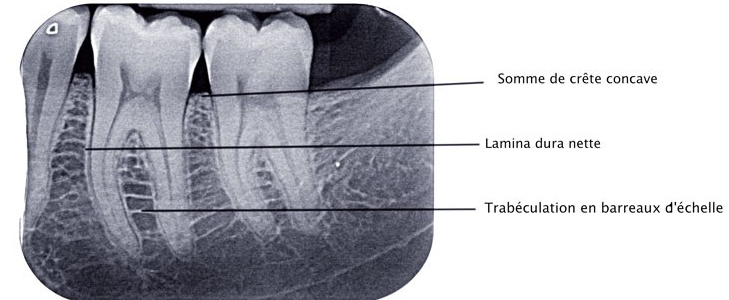

3.4. Aspect radiographique

À la radiographie conventionnelle, le desmodonte se visualise comme une ligne radioclaire fine et régulière séparant :

- La surface radiculaire (radiopaque)

- La lamina dura (ligne radiodense longeant l’alvéole)

Selon PRICHAUD, une image d’épaisseur régulière est un signe de normalité. À l’inverse :

- Un élargissement de l’espace desmodontal évoque une surcharge occlusale, un traumatisme ou une parodontite apicale

- L’absence de l’espace desmodontal signe l’ankylose dento-alvéolaire